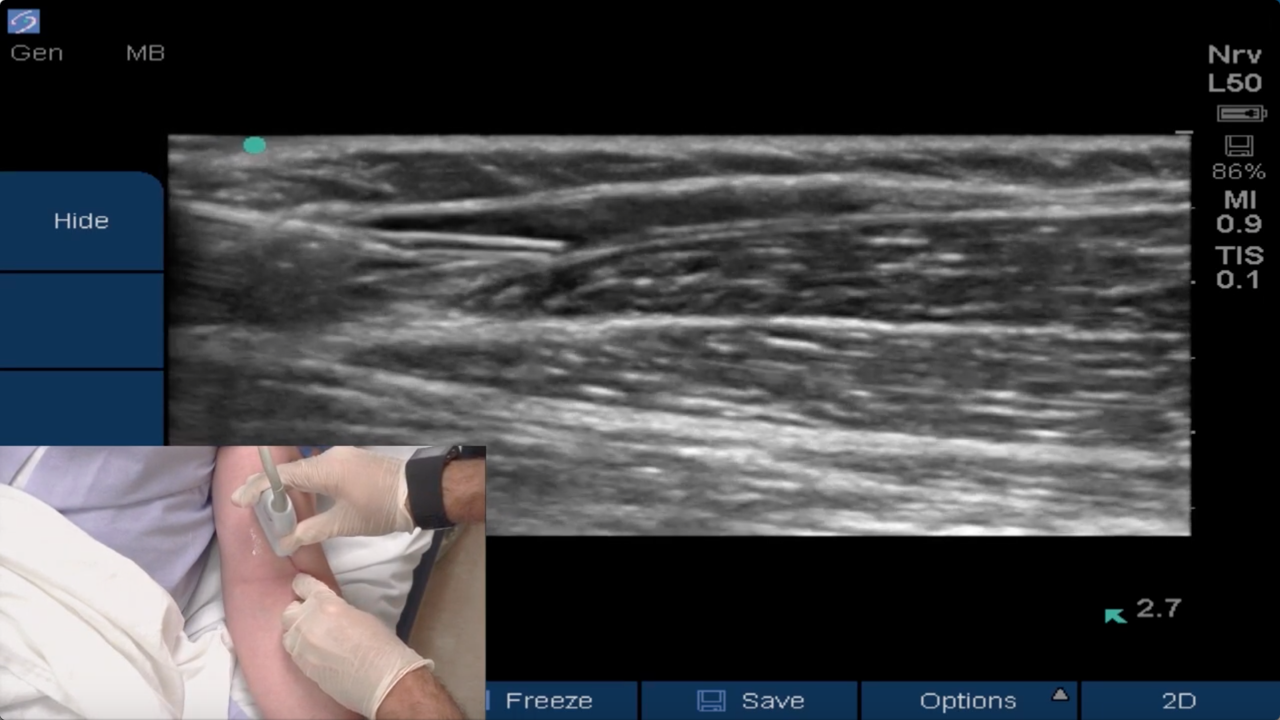

Brandon Winchester demonstrates the placement of an ultrasound guided peripheral IV at the antecubital fossa using a long-axis in-plane technique.